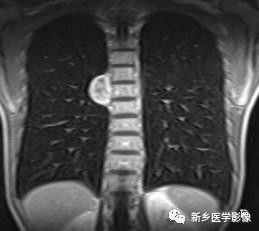

右中纵隔神经鞘瘤CT图像

MRI冠状位T1WI图像示胸椎右旁椭圆形病灶,病灶内部呈混杂信号,边缘呈高信号。